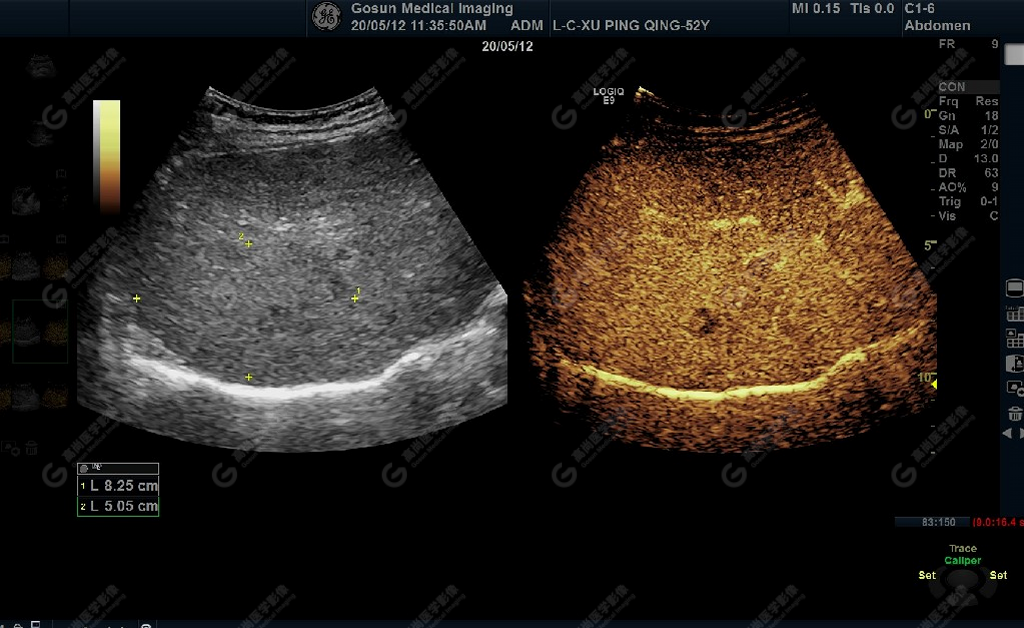

延遲期肝S7局部回聲減低,范圍約82mm×50mm

肝包膜不光滑,實(shí)質(zhì)回聲增粗,不均勻,以右葉顯著,肝內(nèi)可見散在高回聲結(jié)節(jié),最大約7mm×5mm,邊界清,形態(tài)規(guī)則,CDFI顯示高回聲結(jié)節(jié)未見明顯異常血流信號。門靜脈主干內(nèi)徑約14mm,門靜脈右支管腔內(nèi)見實(shí)性低回聲,大小約23mm×14mm,邊界不清,形態(tài)不規(guī)則,局部與肝組織分界不清,CDFI:門靜脈主干血流緩慢,左支血流充盈好,右支血流充盈缺損,低回聲內(nèi)未見明顯血流信號。超聲造影:經(jīng)左側(cè)肘靜脈團(tuán)注超聲造影劑sonovue2.0ml。肝組織開始增強(qiáng)時(shí)間8秒,病灶開始增強(qiáng)時(shí)間11秒,邊界清晰。脈期呈均勻高增強(qiáng),至門脈期和延遲期消退為低增強(qiáng)。延遲期肝S7段局部回聲減低,范圍約82mm×50mm,內(nèi)見一低增強(qiáng)區(qū),范圍約13mm×16mm。